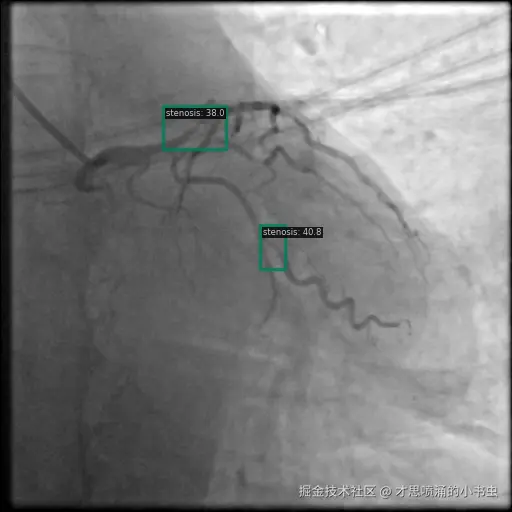

以下图像展示了每个模型在相同冠状动脉造影图像上的表现:

图7 YOLO 检测显示多个具有置信度分数的检测区域。

3.3 YOLO 检测模式

YOLO 通过有效捕获解剖结构同时保持相对高的置信度分数提供了合理的权衡。与基于 transformer 的模型相比,它对小型狭窄区域的检测更好。

如图 7 和图 10 所示,YOLO 的检测模式通常包括具有不同置信度分数的多个区域。这种方法为临床应用提供了精度与召回率之间的合理平衡。

图10 YOLO 检测显示多个具有置信度分数的检测区域。